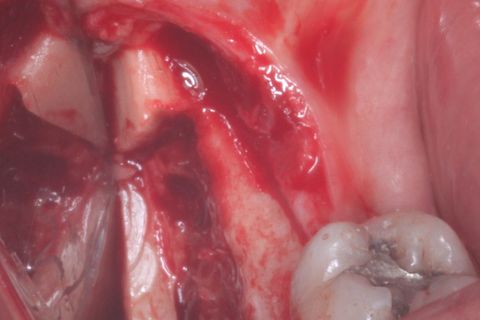

Área doadora: Ramo mandibular ascendente lado direito

Área doadora: Ramo mandibular ascendente lado direito, após a remoção do bloco ósseo.

Bloco ósseo removido.